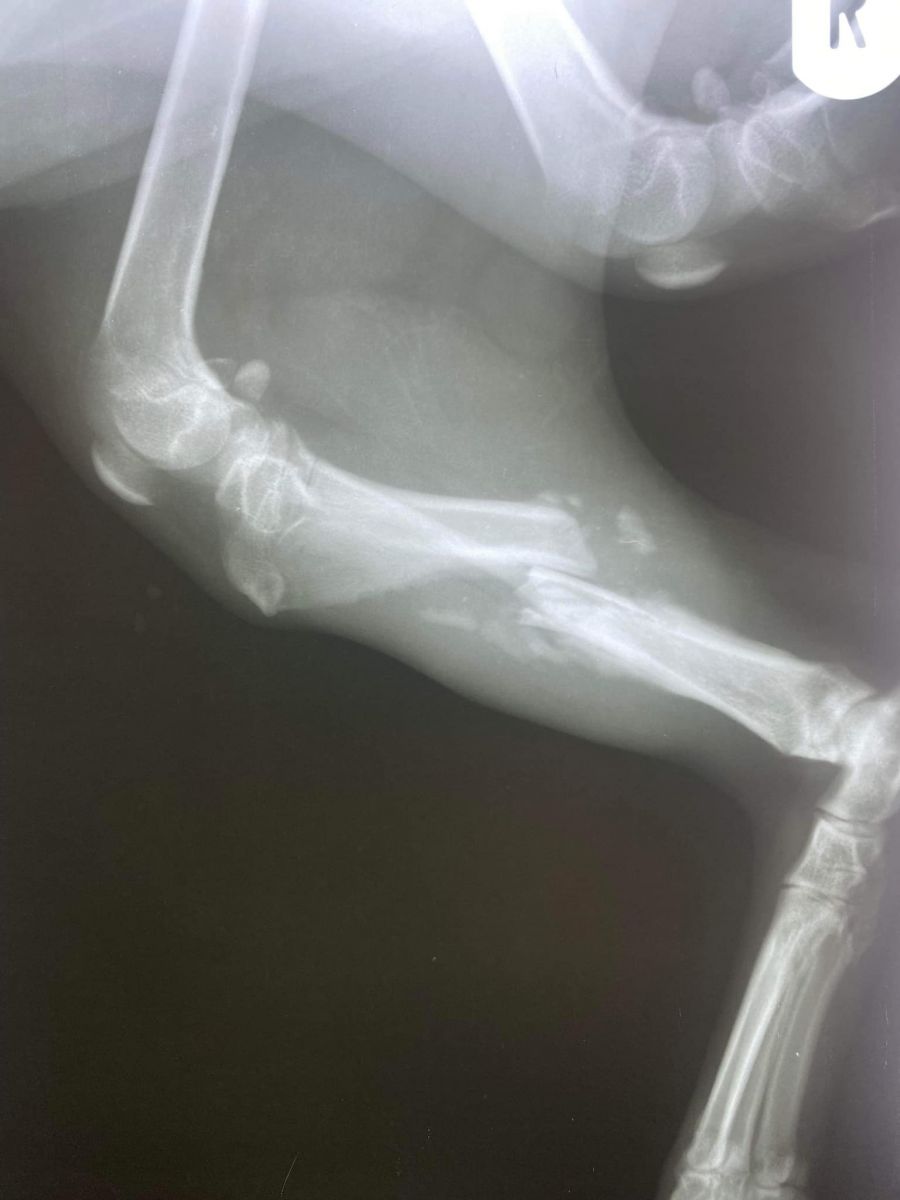

Radiografia a fost trimisă la un cabinet veterinar din Suceava, acolo unde medicul ortoped a spus că există șanse mari pentru recuperarea piciorului, însă numai costul operației este de 1300 lei.

La care se adaugă tratamentul postoperator, care ar ajunge până la minimum 200 de lei.